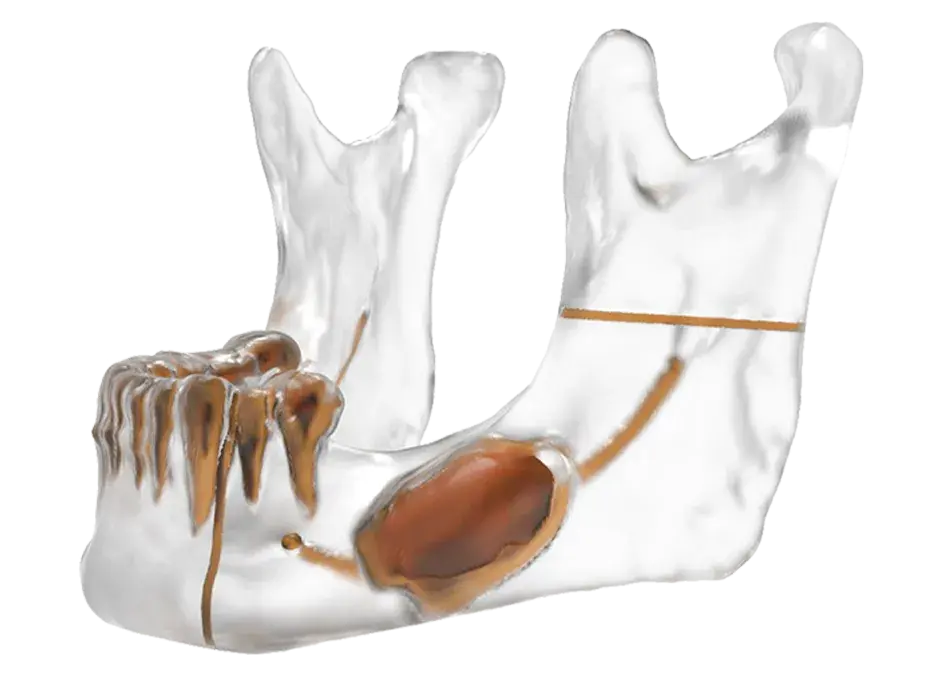

3D Systems' VSP® surgical planning solutions for craniomaxillofacial (CMF) applications received FDA clearance as a service-based approach to personalized surgery over 10 years ago.

3D Systems and Stryker Corporation have partnered to provide surgeons with best-in-class products and services for craniomaxillofacial surgeries. As a leader in personalized healthcare solutions, 3D Systems has planned and delivered devices for more than 140,000 patient-specific cases. The Stryker Craniomaxillofacial business specializes in providing patient-specific options and innovative solutions that help drive efficiencies in surgical suites. The combination of Stryker’s specialized team and advanced implants with 3D Systems' cutting-edge 3D printing technologies and expert consulting services positions both companies to provide a superior level of service to healthcare professionals who use these revolutionary solutions.